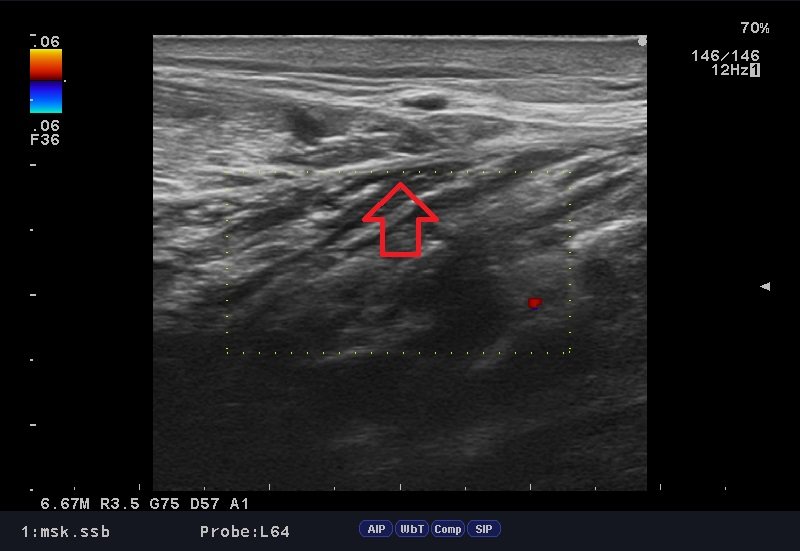

問診後、ストレステストを行い、圧痛点を探し、確認の為、エコー検査。

結果、腓腹筋、ヒラメ筋遠位端部に損傷部位を確認し、「腓腹筋の肉離れ」と確定。

腓腹筋肉ばなれエコー.jpg